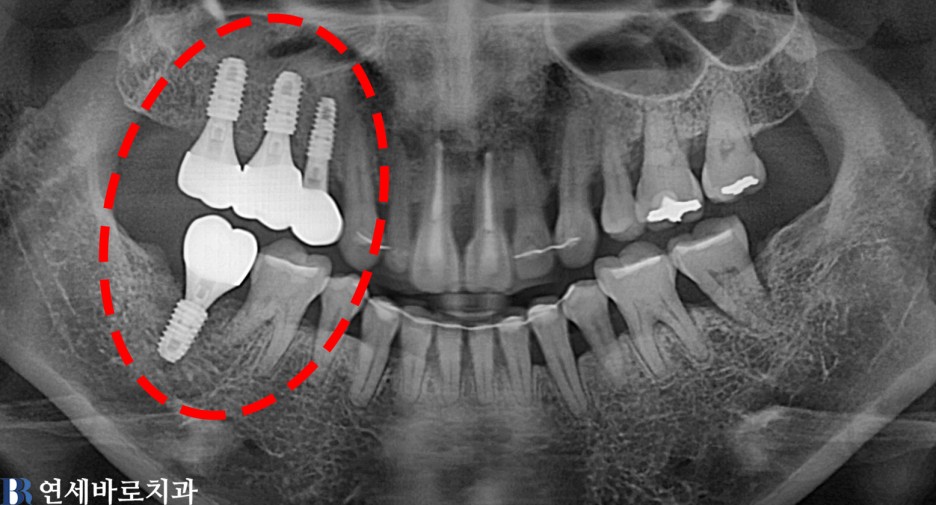

임플란트

어금니 전체 임플란트 #5

양쪽 어금니 임플란트 치료 #2